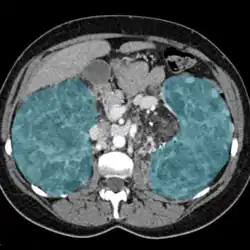

| Enlarged kidneys in blue | |